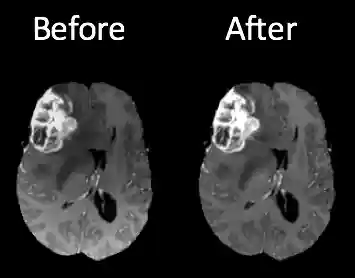

One of the challenges in working with MRI data is dealing with the artifacts produced either by inhomogeneity in the magnetic field or small movements made by the patient during scan time. Oftentimes a bias will be present across the resulting scans (Figure 3), which can effect the segmentation results particularly in the setting of computer-based models.

Figure 3: Brain scans before and after n4ITK bias correction. Notice the higher intensity at the bottom of the image on the right. This can be a source of false positives in a computer segmentation.I employed an n4ITK bias correction on all T1 and T1C images in the dataset (code), which removed the intensity gradient on each scan. Additional image pre-processing requires standardizing the pixel intensities, since MRI intensities are expressed in arbitrary units and may differ significantly between machines used and scan times.